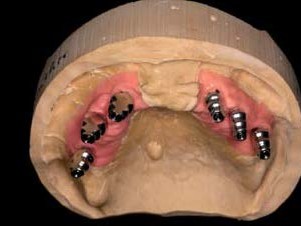

Nach viermonatiger Einheilzeit wurden die Implantate bei reizlosen Weichgewebsverhältnissen freigelegt, Ober- wie Unterkiefer geschlossen und indexiert abgeformt und die Situation mit Zahnfleischmaske auf das Meistermodell übertragen (Abb. 11–14). Die Wahl des geeigneten Abutments richtete sich nach der Dicke der periimplantären Mukosa, wie sie in der Zahnfleischmaske widergespiegelt ist, und der Position der Implantate im Verhältnis zu der ästhetischen Position aus der Wachsaufstellung. Klebebasen waren aufgrund der dünnen periimplantär-mukosalen Verhältnisse ungeeignet. Einteilige Abutments aus Zirkonoxid schieden wegen des Belastungsaspektes im Seitenzahnbereich aus. Die Ästhetik von titannitridbeschichteten Titanabutments kommt bei Teleskopprothesen nicht zur Geltung. Daher waren individuelle Titanabutments die erste Wahl. Nach einer Ästhetikeinprobe wurden die individuellen Abutments auf Basis der gescannten Ober- und Unterkiefermodelle bei ATLANTIS gestaltet und angefertigt. Zur Beschleunigung des Produktionsprozesses wurden die Modelle mithilfe des für ANKYLOS passenden ATLANTIS FLO (Feature Locating Object, DENTSPLYImplants, Mannheim) im Labor gescannt (3Shape D700, Kopenhagen) und die Daten digital übermittelt.

Um die Retentionsflächen zu vergrößern, wurden sie anschließend im Labor mit 120μm Aluminumoxid abgestrahlt (Abb. 15–19). Die individuellen Abutments wurden eingescannt und darauf die Primärteile aus in A3 eingefärbtem Zirkonoxid angefertigt. Design und Herstellung der Zirkonprimärteile erfolgten direkt im Labor (Modellier- Software und Fräseinheit Zirkonzahn, Gais) In der Software wurde die Innenpassung der Primärkronen optimal den jeweiligen Abutments angepasst. Die Parallelität der Teleskope zueinander bzw. die Gesamteinschubrichtung wurden ebenfalls am Bildschirm festgelegt. Die auf einen Konuswinkel von 2 Grad gefrästen Primärteile wurden unter Wasserkühlung im Parallelfräsgerät feingeschliffen und anschließend mit Diamantpolierpaste auf Hochglanz poliert. Eine „spiegelglatte“ Oberflächenqualität der Zirkonoxid-Primärkrone und ein nur minimaler Spalt zwischen Patrize und Matrize von ca. 5 μm sind entscheidend für eine perfekte Funktion. Eine Präzision, die ohne Scannertechnologie und CAD/CAM-Fertigung nicht erzielbar wäre.

Die dadurch erzielte exakte Passung und die hohe Biokompatibilität von Zirkonoxid sind speziell bei Suprakonstruktionen maßgebliche Parameter, um langfristig Komplikationsrisiken in den periimplantären Hart- und Weichgewebestrukturen vermeiden zu können (Abb. 20–21). Die Sekundärteile wurden direkt auf den Zirkonprimärteilen galvanisch abgeschieden. Mit der Galvanotechnik lassen sich hoch präzise und passgenaue Feingoldmatrizen anfertigen, die wesentlich zur lagesicheren Fixierung des Prothesenkörpers beitragen.⁴ Bei der Galvanisierung war unbedingt darauf zu achten, die Schicht Silberleitlack gleichmäßig und nicht zu dick aufzutragen. Hierfür hat sich aus Sicht der Autoren die Airbrush-Technik als alternativlos herausgestellt. Anderenfalls könnte es bereits nach kurzer klinischer Funktionszeit zu einem Haftungsverlust kommen, da die Matrize nur noch punktuell mit der Patrize Kontakt hat. Solche mittels Galvanotechnik hergestellten Sekundärteile für Konusprothesen sind seit über zehn Jahren etabliert.⁶ Die Tertiärstruktur wurde für den Ober- wie den Unterkiefer aus einer Nichtedelmetalllegierung herkömmlich im Modellgussverfahren hergestellt. Noch auf dem Meistermodell wurde das Gerüst auf einen spannungsfreien Sitz hin kontrolliert und mit